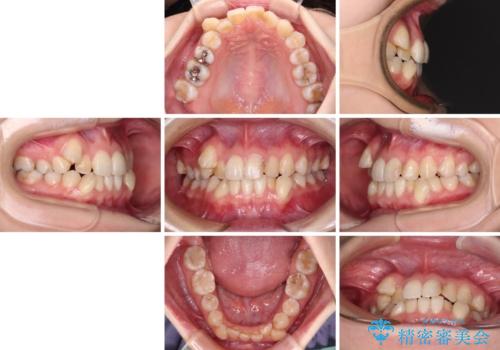

- 上下の八重歯と前歯のデコボコを気にして来院された患者様です。

右上と左下の八重歯が特に著しく、上顎正中が右側にシフトしていました。

デコボコが強いため小臼歯4本を抜歯し、上顎正中を左側に移動させるために補助装置を使用して、ワイヤー装置にて矯正治療を行うこととしました。